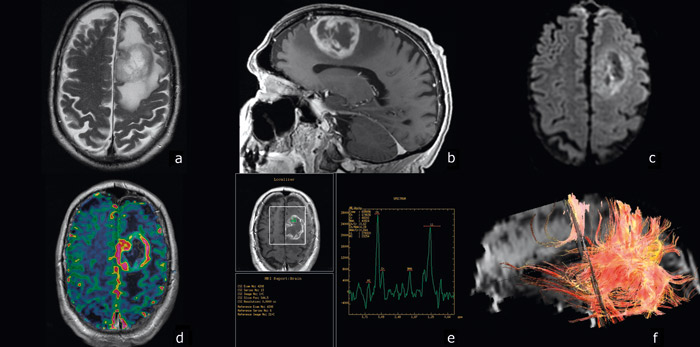

Høygradige gliomer vokser raskt og gir progredierende symptomer som utvikles i løpet av uker eller måneder. Fokale nevrologiske utfall, nyoppstått epilepsi, vedvarende nyoppstått eller endret hodepine eller mental endring hos en voksen bør gi mistanke om hjernesvulst (2). Det bør da gjøres magnetresonanstomografi (MR) med og uten kontrast. Hvis mistanken om hjernesvulst bekreftes, bør pasienten straks henvises til sykehus med spesialister i nevroradiologi og nevrokirurgi, som kan vurdere videre utredning. Blant annet er MR-spektroskopi (MRS) og diffusjonsvektet MR (DWI) nyttig for å skille høygradig gliom fra lavgradig gliom, hjerneinfarkt og hjerneabscess (3). Funksjonell MR (fMRI) og MR-traktografi (DTI) er nyttige preoperative undersøkelser hos pasienter med svulster i nær relasjon til språkområdene, motorisk hjernebark, synsbark og pyramidebanene (fig 1).

Høygradig gliom infiltrerer omkringliggende hjerne, og radikal kirurgi er ikke mulig. Man tilstreber å fjerne svulsten så radikalt som mulig, men med et godt funksjonelt resultat (fig 1). I praksis vil dette si at man fjerner den delen av tumoren som er synlig på kontrastforsterkede MR-bilder. Det er godt dokumentert at kirurgi gir forlenget overlevelse med bevart livskvalitet (10), og pasienten kan oftest mobiliseres raskt etter inngrepet. Når endelig histologisvar foreligger, tas det stilling til eventuell videre onkologisk behandling. Tradisjonelt har man vært tilbakeholden med kirurgisk behandling av høygradige gliomer hos eldre pasienter, men våre egne og andres data tyder på at også eldre i god allmenntilstand profitterer på operasjon og at den eldre aldersgruppen muligens underbehandles (13, 14).